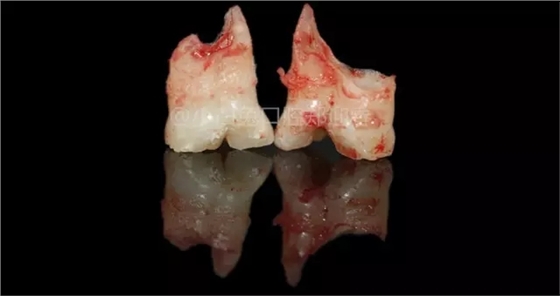

拔出后的離體牙

6、由于融合發(fā)生的時(shí)期不同,就會(huì)表現(xiàn)出各種融合的類型:牙冠、牙根和牙髓腔都融合為一的;牙冠融合、牙根分開、髓腔根管各一的;牙冠分開、牙根融合。所融合的兩個(gè)牙,可以都是正常牙,如發(fā)生在乳側(cè)切牙和乳尖牙之間的融合;也可以是正常牙和多生牙之間的融合,例如乳側(cè)切牙和多生牙融合。

7、融合牙是由兩個(gè)或兩個(gè)以上正常牙胚融合而成牙齒可以完全融合也可以僅為冠融合或根融合,但牙本質(zhì)是連通的無論是乳牙還是恒牙均可發(fā)生融合牙,最常見于下頜乳切牙,有融合牙的牙列中牙齒數(shù)目相應(yīng)減少;雙生牙是牙齒發(fā)生期中由一個(gè)牙胚分裂為二而形成的畸形,通常為完全或不完全分開的牙冠有一個(gè)共同的牙根和根管,常見于下頜乳切牙,雙生乳牙常伴有其繼承恒牙的先天性缺失;結(jié)合牙為兩個(gè)牙齒的牙根發(fā)育完全以后發(fā)生粘連的牙其牙本質(zhì)是分開的僅是兩個(gè)牙齒的牙根,偶見牙骨質(zhì)粘連而結(jié)合偶見于上頜第二和第三磨牙區(qū)。